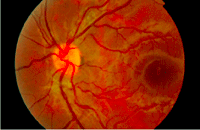

Figura 19. Hombre de 27 años que consulta por pérdida de visión en su ojo derecho. En la oftalmoscopia se observan áreas de vasculitis y edema con necrosis en polo posterior.